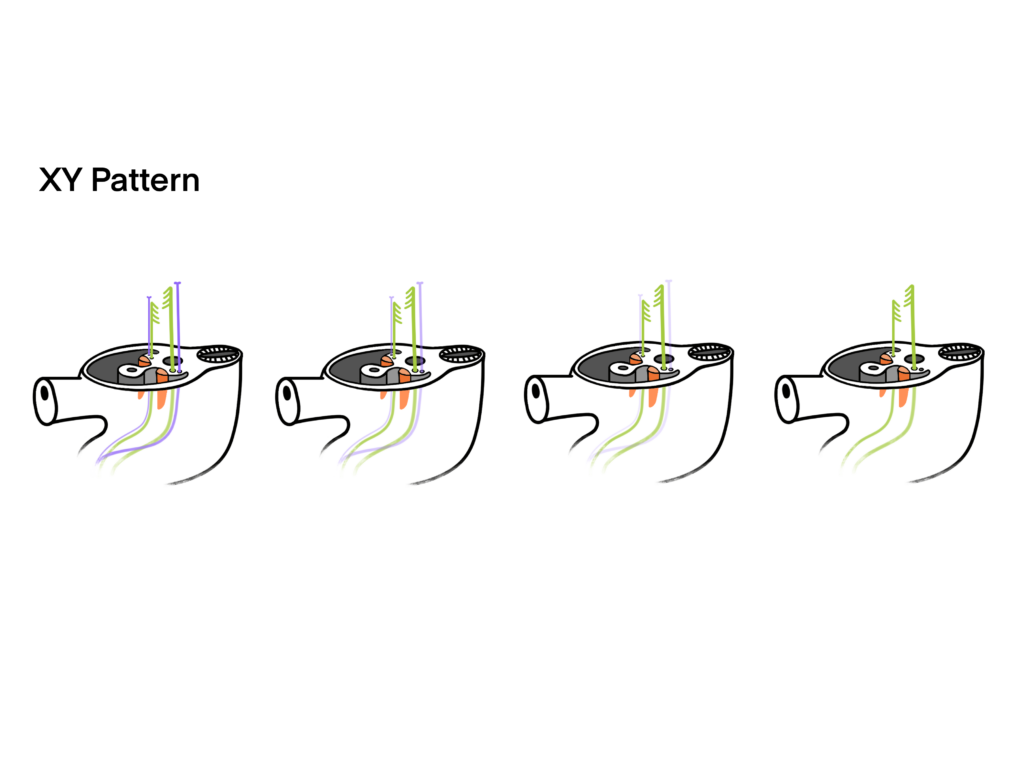

Development of the Genital System